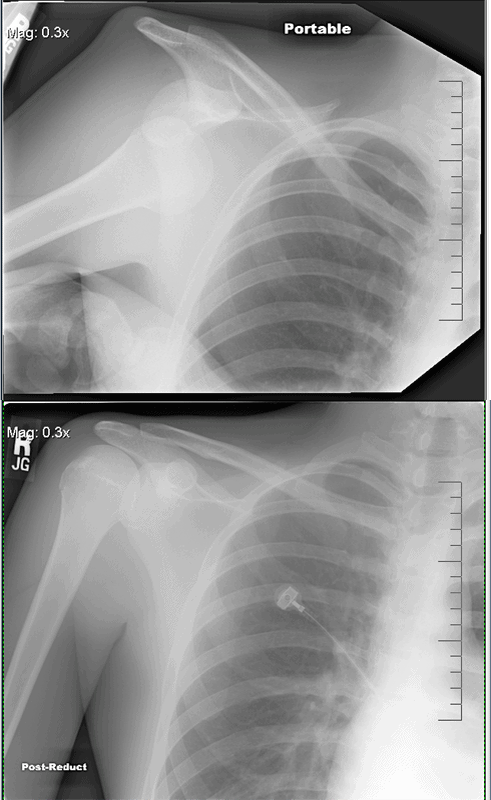

14. Вывих плеча до и после того, как его вернули на место